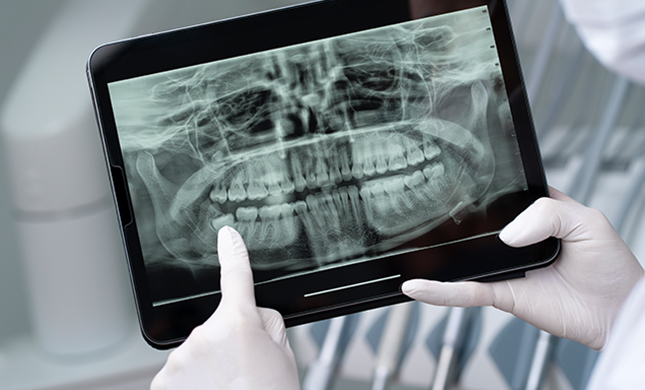

1. Pantomogram (ortopantomogram, OPG)

Pantomogram to zdjęcie rentgenowskie całej twarzoczaszki, obejmujące kości szczęki, żuchwy oraz zęby. Jest to badanie dwuwymiarowe, które pozwala uzyskać szeroki wgląd w stan struktur anatomicznych w obrębie jamy ustnej oraz okolicznych tkanek. Pantomogram umożliwia:

•  Ocena anatomicznych struktur – widoczność zębów, przyzębia, korzeni zębów.

•  Wykrywanie nieprawidłowości – zęby zatrzymane, zmiany patologiczne, takie jak ubytki próchnicowe czy zapalenia w obrębie korzeni.

•  Obserwacja rozwoju u dzieci – pozwala na analizę zawiązków zębów oraz ocenę stopnia ich rozwoju.

•  Monitorowanie postępu leczenia ortodontycznego – umożliwia ocenę zmian w położeniu korzeni zębów, efekty leczenia, a także daje możliwość planowania dalszego postępowania.

Zdjęcie to może być powtarzane w trakcie leczenia ortodontycznego, co daje możliwość monitorowania efektów leczenia i wprowadzenia korekt w planie terapeutycznym.

>  Zdjęcie pantomograficzne.